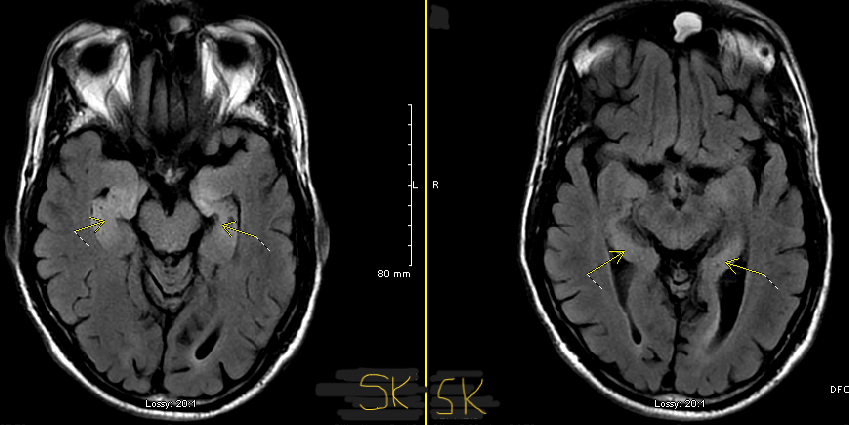

Who believes in SREAT ? Just a naive neurology resident who has seen 2 cases of abnormal MRI, inflammatory tap, high tpo Ab and otherwise broadly negative work up with rapid improvement post steroids trying to figure out if I am a SREAT believer or nonbeliever. 🙈 #Neurology